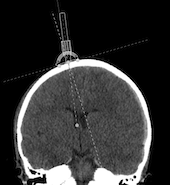

For a controlled placement of the ventricular catheter, the THOMAL GUIDE is placed directly on the skull bone with three feet and with the line markings parallel to the centerline above the drill hole to ensure a right angle of insertion in the sagittal plane. In the coronal plane, an individual angle can be determined using an angle adjustment on the THOMAL GUIDE. The rotation of the catheter guide, which is guided over the rails, is done via a pivot point located very close above the borehole.

1. The most precise method for determining the individual insertion angle of the ventricular catheter requires the reading of a volume or thin-film data set into a planning software. In this software the optimal trajectory for the ventricular catheter can be defined. The coordinates of the entry point, e.g. to the nasion and the centerline, can be measured. At the entry point, the tangent would have to be drawn in the projected coronal plane and the angle of the trajectory to the tangent measured. Now the data of the entry point can be transferred to the patient and intraoperatively the angle can be applied on the THOMAL GUIDE for the insertion of the catheter. This method is especially recommended for very narrow ventricle systems. The accuracy of determining the angle depends on the image used.

A coronary sectional image should be used to facilitate individual measurement of the angle of entry. If possible, this should be at the level of the anterior horn in front of the Foramen Monroi. The entry point, the projected target point and the projected trajectory should be marked on the foramen monroi. To mark the projected target point, the distance to the midline and the depth of the ventricle should be taken into account. Now the tangent can be drawn. The easiest way to do this is to set two points at equal distances medially and laterally from the entry point. The connection of these two points corresponds to the tangent. Accordingly, the angle between the trajectory and the tangent can then be determined and set on the THOMAL GUIDE.